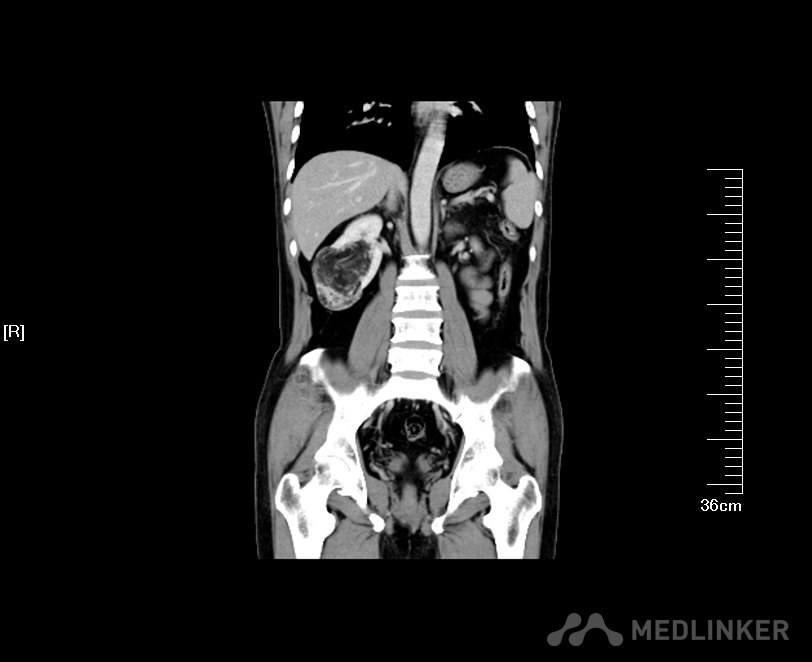

病例一 肾肿瘤患者(肿瘤大于4cm) 2016年02月手术患者,女,28岁,宜兴人,体检发现右肾占位5年,伴加重4月入院,患者5年前发现右肾错构瘤约2.0cm左右,每年于基层医院复查CT平扫检查,均未进行CT增强检查,肿瘤大小一直提示2.0cm左右,4月前单位体检B超发现右肾占位6.0cm左右,遂来我院复查彩色B超提示右肾上极高回声5.8*2.0cm,CT增强检查提示右肾肿瘤呈分叶状生长,突出肾脏表面约2.0cm左右,不排除肾癌可能;遂住院进一步治疗。术前GFR:左侧44.2ml/min,右侧51.3ml/min。术前诊断:右肾肿瘤;经讨论认为患者既往有右肾错构瘤良性肿瘤病史,近期肿瘤增大且呈现恶变倾向,考虑患者较为年轻,虽然肿瘤远大于4.0cm,为尽力争取保护其右肾,决定行腹腔镜下保留肾单位的右肾部分切除术。 我院彩色B超根据肿瘤血流情况判断肿瘤远非2.0cm,而是5.8*2.0cm左右

根据术前影像学检查术中精准定位右肾上极肿瘤